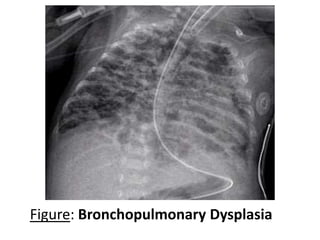

 Chest X-ray : Shows streaky interstitial markings,

patchy atelectasis intermingled with cystic area and

severe overall lung hyperinflation.

Figure: Bronchopulmonary Dysplasia